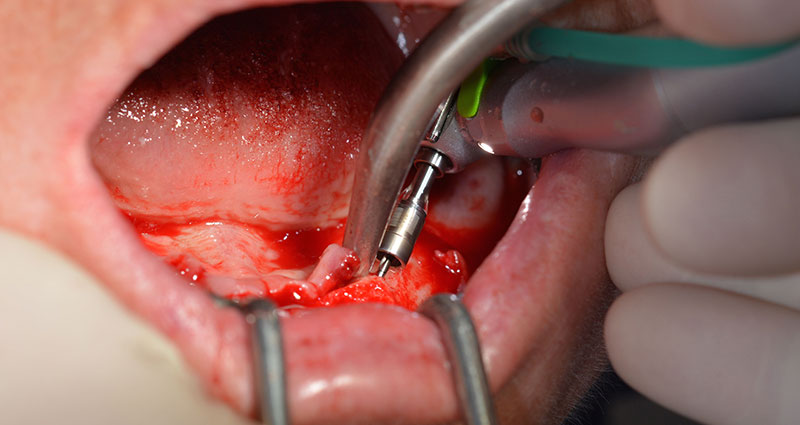

Хирургичният протокол за избраните импланти (SKY, bredent medical) изисква обороти от 1,200 rpm за пилотно пробиване с борера (Фиг. 7 - 9).

Това кореспондира със следващата зададена програма на Implantmed. Тук виждаме обратния наконечник на W&H под наклон от 45° ъгъл мезиокаодално в областта на 45, с цел да се предпази менталният нерв. Изходът на менталния нерв е използван като анатомична препратка за всички пробивания в тази зона. Следващите отвори са пробити при намалени обороти от 300 rpm (Фиг. 10 и 11).